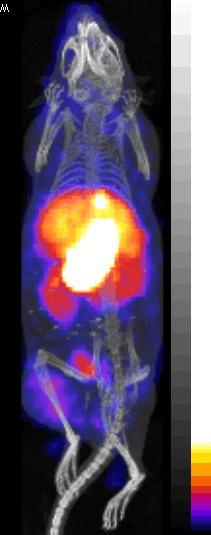

[18F]NaF Bone Scanning

[64Cu] labeled Peptide tumor image